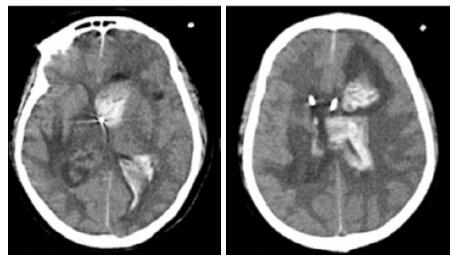

| A:右侧丘脑、左侧岛叶病变,伴脑室扩张;B:双侧脑室钻孔引流术后改变,脑室扩张较前(2019-09-29)好转,右侧丘脑、左侧岛叶病变伴出血 图 2 患者2019-09-29头颅CT平扫(A)和2019-09-30头颅CT平扫(B) |

转入ICU后呼吸机辅助通气、甘露醇100 mL/8 h静滴脱水、头孢呋辛1.5 g/12 h静滴抗感染,肠内营养等支持治疗。当晚血常规:白细胞13.3×109/L,中性粒细胞百分比85.3%,C反应蛋白17.1 mg/L,降钙素原0.64 ng/mL。脑室外引流术后次日血化验:白细胞16.6×109/L,中性粒细胞百分比92.8%,C反应蛋白78.4 mg/L;从脑室外引流管留取脑脊液检验:有核细胞6×106/L,红细胞1 960×106/L,蛋白含量1.717 g/L,葡萄糖4.72 mmol/L,细菌培养阴性,涂片未找到细菌;复查头颅CT示:脑室扩张好转,右侧丘脑、左侧岛叶病变伴出血(图 2);胸部CT示,两肺间质性肺炎下叶为著,较前(2019年6月21日)部分好转(图 3)。考虑到炎症指标升高,遂改哌拉西林他唑巴坦3.375 g/12 h静滴抗感染。此后经脑室外引流管反复留取脑脊液送检涂片及培养均阴性。术后第5天行“导航下立体定向颅内病灶活检术+双侧omaya囊置入术”,术中穿刺液呈黄色黏稠脓性,考虑脑脓肿,留取脓液送高通量测序(next-generation sequencing, NGS),并升级为美罗培南2 g/8 h联合利奈唑胺0.6 g/12 h静滴抗感染治疗。术后第7天患者突发血压升高、瞳孔不等大,昏迷程度加深;急查头颅CT示,双侧脑室钻孔引流术后改变,双侧侧脑室引流管走形区出血伴血肿形成;右侧丘脑区积液、积血,双侧脑室积血新发(图 4),甘露醇加量至250 mL/8 h联合地塞米松5 mg/6 h静滴加强脱水;当日术中脓液高通量测序结果回报:皮疽诺卡菌(序列数52 867个)、支气管戈登菌(序列数10个)。确诊脑诺卡菌病,抗菌治疗方案改为亚胺培南西司他丁0.5 g/6 h静滴,联合利奈唑胺0.6 g/12 h和复方磺胺甲恶唑片(0.48 g/片)3片/6 h口服。此后患者仍伴低热,炎症指标呈上升趋势。术后2周患者再次突发血压升高、瞳孔不等大、对光反射消失、神志深昏迷,急查头颅CT示再发脑疝(图 5),急诊行“去骨瓣减压术+脑内血肿清除术”,术后患者仍呈深昏迷状态,双侧瞳孔散大、对光反射消失,次日自动出院。